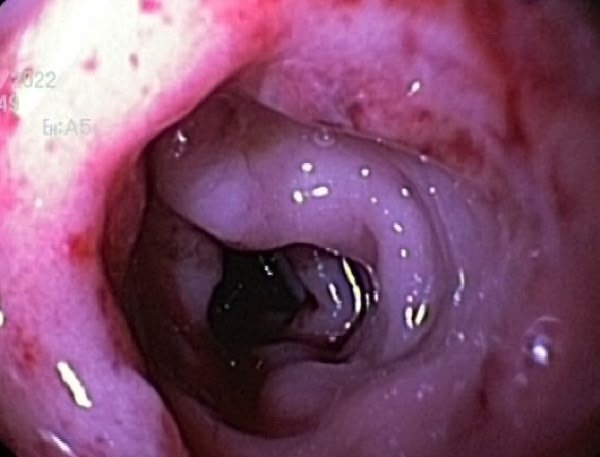

Trois cas résultent de l'extension d'une otite. Ces patients étaient présentés pour ataxie et l'un d'entre eux présentait également des crises convulsives partielles. Dans les trois cas, un examen scanner a mis en évidence une otite moyenne associée à une lésion intracrânienne extra-axiale adjacente, évoquant un empyème méningé. Dans le premier cas, un traitement antibiotique probabiliste permet la résolution des signes cliniques. Dans le deuxième cas, des prélèvements par vidéo-otoscopie permet d'identifier la présence de Staphylococcus felis. Un traitement antibiotique ciblé entraîne la résolution des signes cliniques. Dans le troisième cas, l'examen vidéo-otoscopique permet l'identification de Pseudomonas spp. Malgré une antibiothérapie adaptée, l'état clinique du patient se détériore. Un nouvel examen scanner montre une aggravation de l'empyème méningé. Une craniotomie est réalisée et permet le débridement de l'empyème. Cette intervention, associée à une corticothérapie et la poursuite de l'antibiothérapie, permettent la résolution des signes cliniques.

Nous présentons également un cas d'extension d'une rhino-sinusite infectieuse chez un chat présentant une ataxie. Un scanner montre des lésions naso-sinusales agressives avec lyse de la paroi sinusale frontale et empyème méningé adjacent. Une trépanation du sinus frontal permet de réaliser des prélèvements pour analyses bactériologiques et mycologiques. Un traitement antibiotique ciblé permet une bonne évolution clinique.